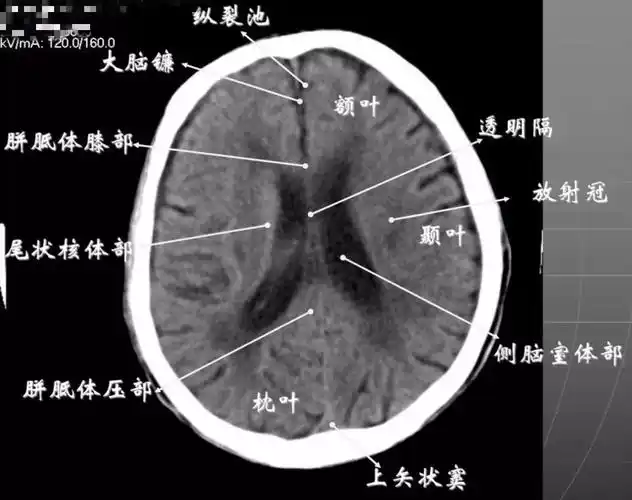

头颅ct解剖与常见出血梗死判读

头部ct影像解剖